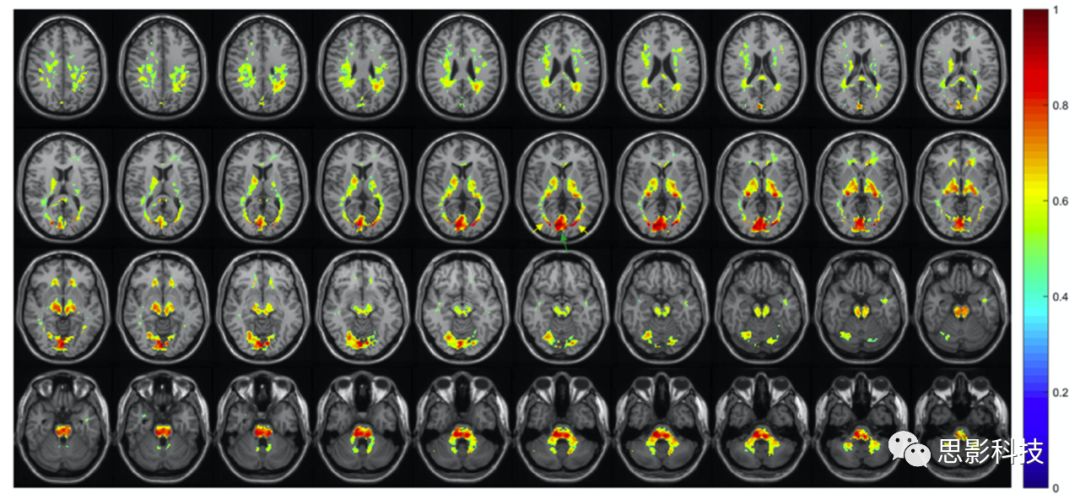

進一步的研究需要驗證WM束是否直接與大腦皮層區(qū)域的神經(jīng)元活動相關這個假設。Ding等人分析了一組健康被試的3T掃描所得的靜息態(tài)BOLD數(shù)據(jù)和DTI數(shù)據(jù)。然后,他們尋找特定的GM體積及分割出來的WM區(qū)域之間的相關性。所得的圖像均配準到MNI空間。使用Johs Hopkin圖譜分割出48WM腦區(qū),使用PickAtlas工具分割出84BA GM腦區(qū)。然后計算每個WMGM之間的Pearson相關性,進而得到一個功能相關矩陣。

12顯示了48WM區(qū)和84GM區(qū)中BOLD信號在靜息態(tài)下的平均時間相關性,矩陣中每個值表示12個被試中所對應的WMGM之間的平均相關系數(shù)值。很明顯,該相關系數(shù)的變化不是隨機的,而是以橫條紋的形式表現(xiàn)出來的,這表明某些WM束與GM總體上表現(xiàn)出更大的時間序列相關性。部分WM束與GM區(qū)域之間也存在負相關。最值得注意的是,左側tapetum白質與大多數(shù)GM區(qū)域呈顯著的負相關(平均CC < -0.3)。水平條紋的模式表明,在大腦處于靜息態(tài)下,部分WMGM存在同步的BOLD反應。

Fig 12 12HC被試中,WM(垂直軸)GM區(qū)域(水平軸)BOLD信號的平均時間相關矩陣。

Ding等人進一步分析了1723T靜息態(tài)fMRI數(shù)據(jù)。GM區(qū)域取自于預處理所得的ROI,包括68個腦溝和腦回。同時,WM區(qū)來自JHU ICBM-DTI-81 WM圖譜,包括48WM腦區(qū)。靜息態(tài)fMRI信號為每個GMWM區(qū)之間的平均時間序列信號值 (13)。這些數(shù)據(jù)重現(xiàn)了早期的、樣本量較小的研究結果,并強烈建議對不同組之間的功能相關矩陣進行比較是有意義的。例如,假設GM-WM相關模式在大腦發(fā)育或退化過程中會發(fā)生改變是合理的,這可能為描述不同疾病的大腦功能變化提供一種新的方式。Ji等人報道了一個相似的研究,通過WM的兩兩ROI相關建立了一個功能網(wǎng)絡,并得出了與帕金森病患者功能障礙相關的拓撲屬性的結果。

Fig 13 172名年輕人中,48WM(縱軸)68個皮層區(qū)域(橫軸)的相關性矩陣。